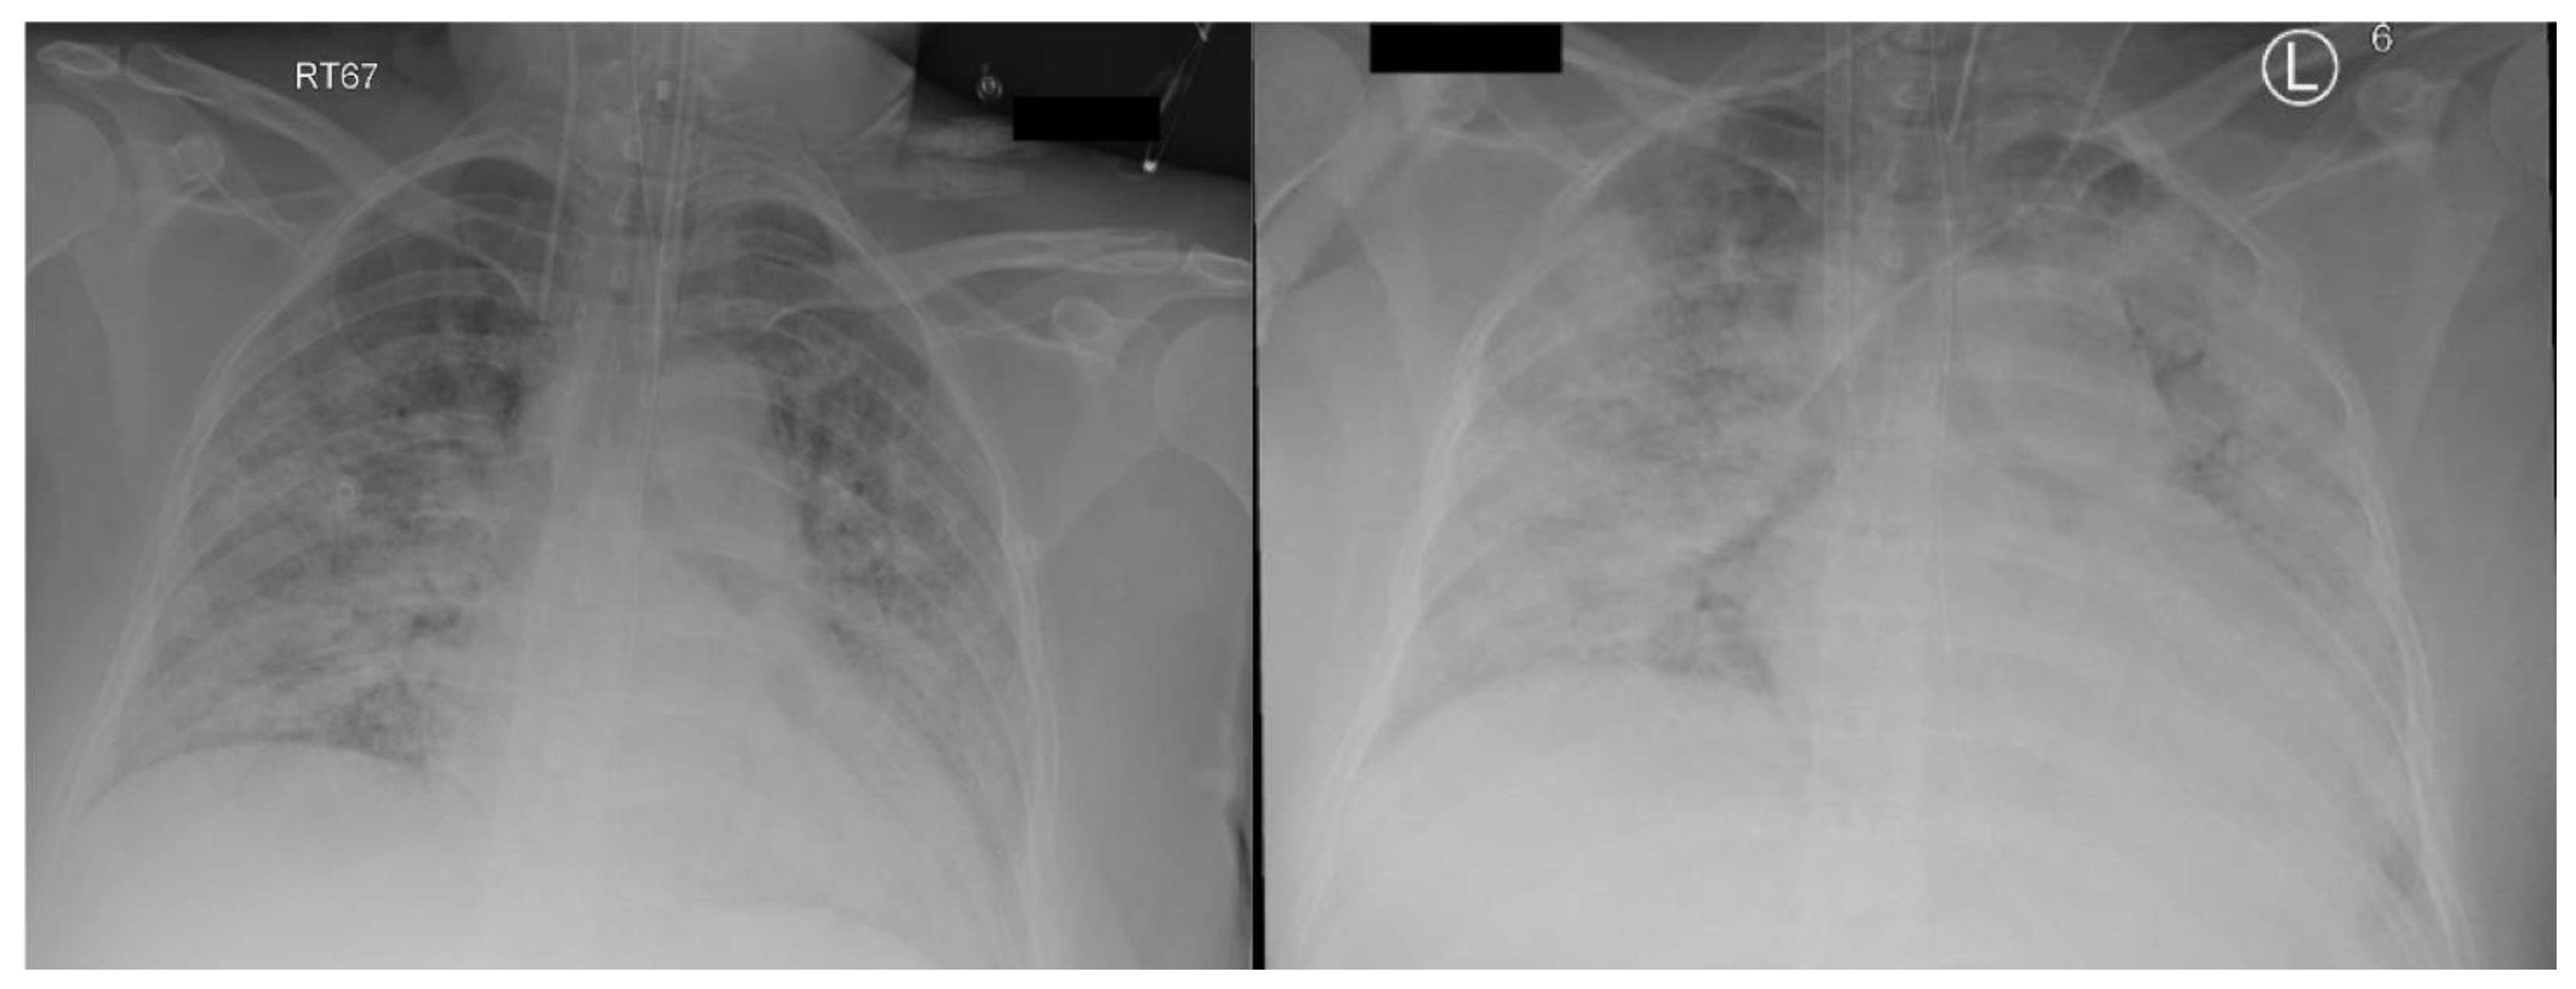

Following hospital admission, she rapidly deteriorated, requiring invasive mechanical ventilation, and was immediately transferred to our center for respiratory failure management. She was sedated with Fentanyl and Propofol infusions. She was hemodynamically stable and had normal renal and liver function. The lung-protective strategy was applied with the following parameters: pressure control ventilation (PCV) with driving pressure (DP) of 16 cm H2O and positive end expiratory pressure (PEEP) of 12 cm H2O, FiO2 of 0.7, inspiratory time of one second, and respiratory rate of 20 breath/minute. Initial arterial blood gas showed a pH of 7.43, PaO2 of 8.0 Kpa (60 mmHg), PaCO2 of 4.6 Kpa (34.5 mmHg), and HCO3 of 23.2 mmol/L. Chest X-ray (Figure 1 left) was consistent with bilateral airspace infiltrates. She was started on treatment as per National Guidelines for Management of COVID-19 in the Kingdom of Saudi Arabia, which included Dexamethasone 6 mg daily. However, due to clinical and biochemical evidence of potential cytokine storm and the goal of optimizing fetal lung maturity, the Dexamethasone dose was increased from day two to 20 mg BID for 5 days, then once daily thereafter. Meropenem, Vancomycin and Azithromycin were given for suspected secondary bacterial pneumonia, as the initial procalcitonin level was 64 ng/mL. She received Convalescent plasma, in addition to Tocilizumab, after exclusion of bacterial sepsis.

The initial ECMO flow was 4.3 L/min at RPM of 3500, and sweep gas flow was 3 L/min. The ventilator parameters were changed to “rest” setting, with a DP of 10, PEEP of 12 cm H2O keeping tidal volume at 2–3 mL/kg, and RR at 10/min. Heparin infusion was started as per our ECMO anticoagulation protocol, which targeted unfractionated heparin levels between 0.2 and 0.4 U/mL. Fresh frozen plasma was given when antithrombin activity was less than 60%. While the patient was on ECMO, she continued to have severe hypoxemia, requiring FiO2 0.9 and 1.0 on the ventilator and ECMO, respectively. Recirculation between the two ECMO cannulas was ruled out by pre- and post-oxygenator blood gases. The distance between the tips of the cannulas on X-ray was approximately 15 cm. The chest X-ray showed worsening widespread bilateral lung infiltrate (Figure 1 right) and the patient was started on diuretics to target negative fluid balance.

Figure 1. CXR (left) on admission, (right) on ECMO day 0.